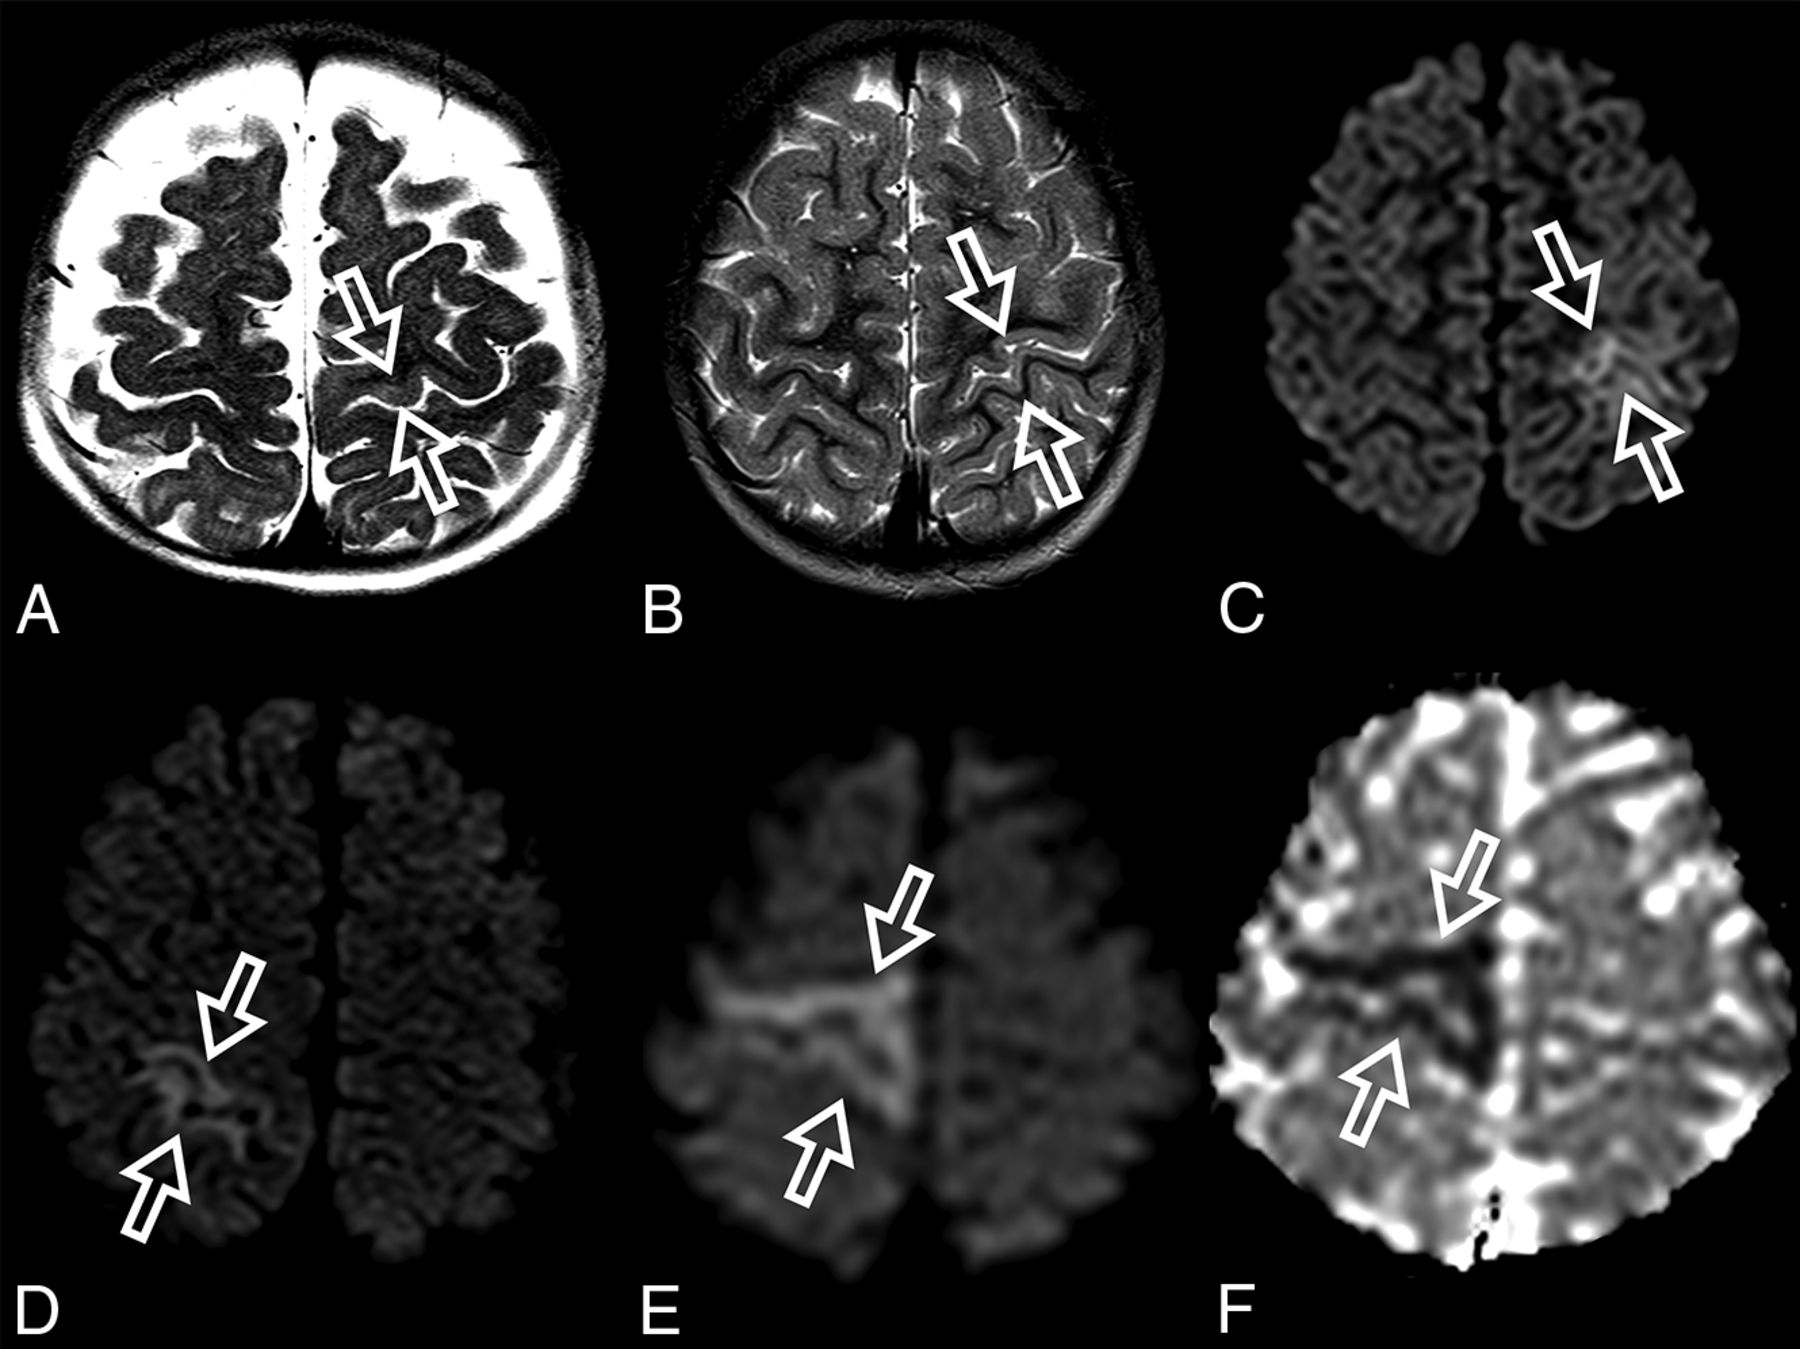

At diagnosis, brain MR imaging findings were abnormal in most patients (n = 12, 92%). The most common brain MR imaging findings were unilateral or bilateral perirolandic signal changes (n = 7, 54%) (Fig 1) and unilateral or bilateral thalamic signal changes (n = 10, 77%) (Fig 2). Perirolandic signal abnormalities were unilateral in most cases (n = 5, 71%) and were more frequently seen only affecting the precentral or both the pre- and postcentral gyri. Half of the thalamic changes were unilateral (n = 5, 50%). Simultaneous perirolandic and thalamic signal changes occurred in 6 patients (n = 6, 46%). An association of EPC (clinically/EEG) and perirolandic signal changes was present in 6 patients (n = 6, 75%), and an association of EPC (clinically/EEG) and thalamic signal changes, in 7 patients (n = 7, 87.5%). Two patients with EPC (clinically/EEG) did not present with perirolandic signal abnormalities. The findings positive for lesions overall were on the DWI of 10 patients (n = 10, 83%), on the T2WI of 9 patients (n = 9, 75%), and on FLAIR of 7 patients (n = 7, 58%). In 4 patients, DWI was the only sequence with abnormal findings. The occipital lobe was affected in the early brain MR imaging in 2 patients (n = 2, 15%). Signal changes in other brain regions were found in 5 patients (n = 5, 42%), involving multiple regions, namely the cerebral white matter, insula, putamen, caudate nucleus, fornix, cerebellar vermis, and also the frontal and occipital lobes. One patient did not present with either perirolandic or thalamic changes but instead presented with a diffuse pattern similar to that of leukoencephalopathy, with restricted diffusion in the white matter and white matter tracts (Fig 3). Three patients had an abnormally high lactate peak on MR spectroscopy. None of our patients had ASL or other perfusion-weighted imaging at the time of diagnosis. T1 and T2* imaging and SWI had negative findings at the time of diagnosis.

ADC map images of a 7-month-year old male with POLG-related disorder, demonstrating a diffuse pattern of leukoencephalopathy with restricted diffusion of the periventricular white matter of the bilateral temporal lobes in A, the occipital lobes in B, and also of the bilateral fornix in C and corpus callosum in D.